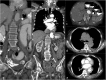

Objectives: To demonstrate the various presentations of acute aortic pathology and to present diagnostic and therapeutic approaches.

Methods: Diagnostic imaging is the key to the reliable diagnosis of acute aortic pathology with multi-slice computed tomography angiography (CTA) as the fastest and most robust modality. Endovascular aortic repair (EVAR) with stent grafts and open surgical repair are therapeutic approaches for aortic pathology.

Results: CTA is reliable in diagnosing and grading aortic trauma, measuring aortic diameter in aortic aneurysms and detecting vascular wall pathology in acute aortic syndrome and aortic inflammation. CTA enables planning the optimal therapeutic approach. Stent graft implantation and/or an open surgical approach can address vascular wall pathology and exclude aortic aneurysms.

Conclusion: Aortic emergencies have to be detected quickly. CTA is the imaging method of choice and helps to decide whether elective, urgent or emergent treatment is necessary with EVAR and open surgical repair as the main treatment approaches.

Teaching points: • To present aortic pathology caused by trauma • To present acute aortic syndrome (aortic dissection, intramural haematoma and penetrating ulcers) • To present symptomatic and ruptured aortic aneurysm • To present infection (mycotic aneurysms/aorto-duodenal fistulae) or iatrogenic injury of the aorta • To understand different presentations for treatment planning (EVAR and open surgery).